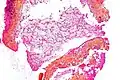

| Tinción | Tipo | Características | Uso | Ejemplo |

|---|---|---|---|---|

| Tinción tricrómica de Masson | Tricrómica |

|

Se tiñen fibras, tejido muscular y citoplasmas, donde destaca esencialmente el condrioma como un fino granulado rojizo. Sin embargo, por su pH ácido, que se encuentra entre 2.5 y 2.7 (ligeramente por encima del óptimo para la tinción del colágeno), se presenta como una tinción incompleta y difusa del componente fibrilar más fino (membrana basal y finas fibras reticulares). |